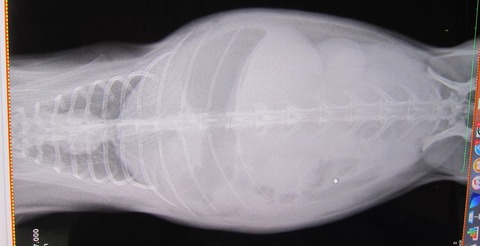

9日の譲渡会、

とてもよく食べ、なでなでアピール頑張ってたかぐらちゃん

排泄物もお見事でした

最中は上の画像の通りの排泄物に、たくさんナデナデして頂き、

帰宅、すぐのご飯も完食したのち、第2ご飯の催促もご覧の通りで…

心配なし、問題なし、

や、ケージかじるのは歯に悪いから問題ありですが…(・・;)

食べることが大好きなかぐらちゃん

ナデナデも大好きですよぉ【だるまうさぎレスキュー・別館】も覗いてみて下さいね